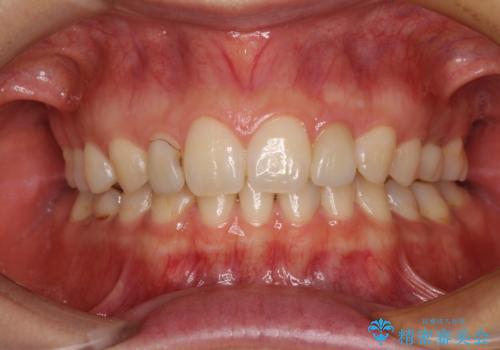

- ラミネートベニアと歯の境目の着色を気にして来院された患者様です。

矯正治療後に矮小歯であった歯をラミネートベニアにて形を変えたそうですが、矯正歯科治療直後であったためか、歯肉の位置が変わったことで境目が見えていました。